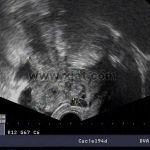

1、(急性)全景四维彩超+血常规

2、(慢性)阴道四维彩超+动态数字化子宫输卵管碘油造影